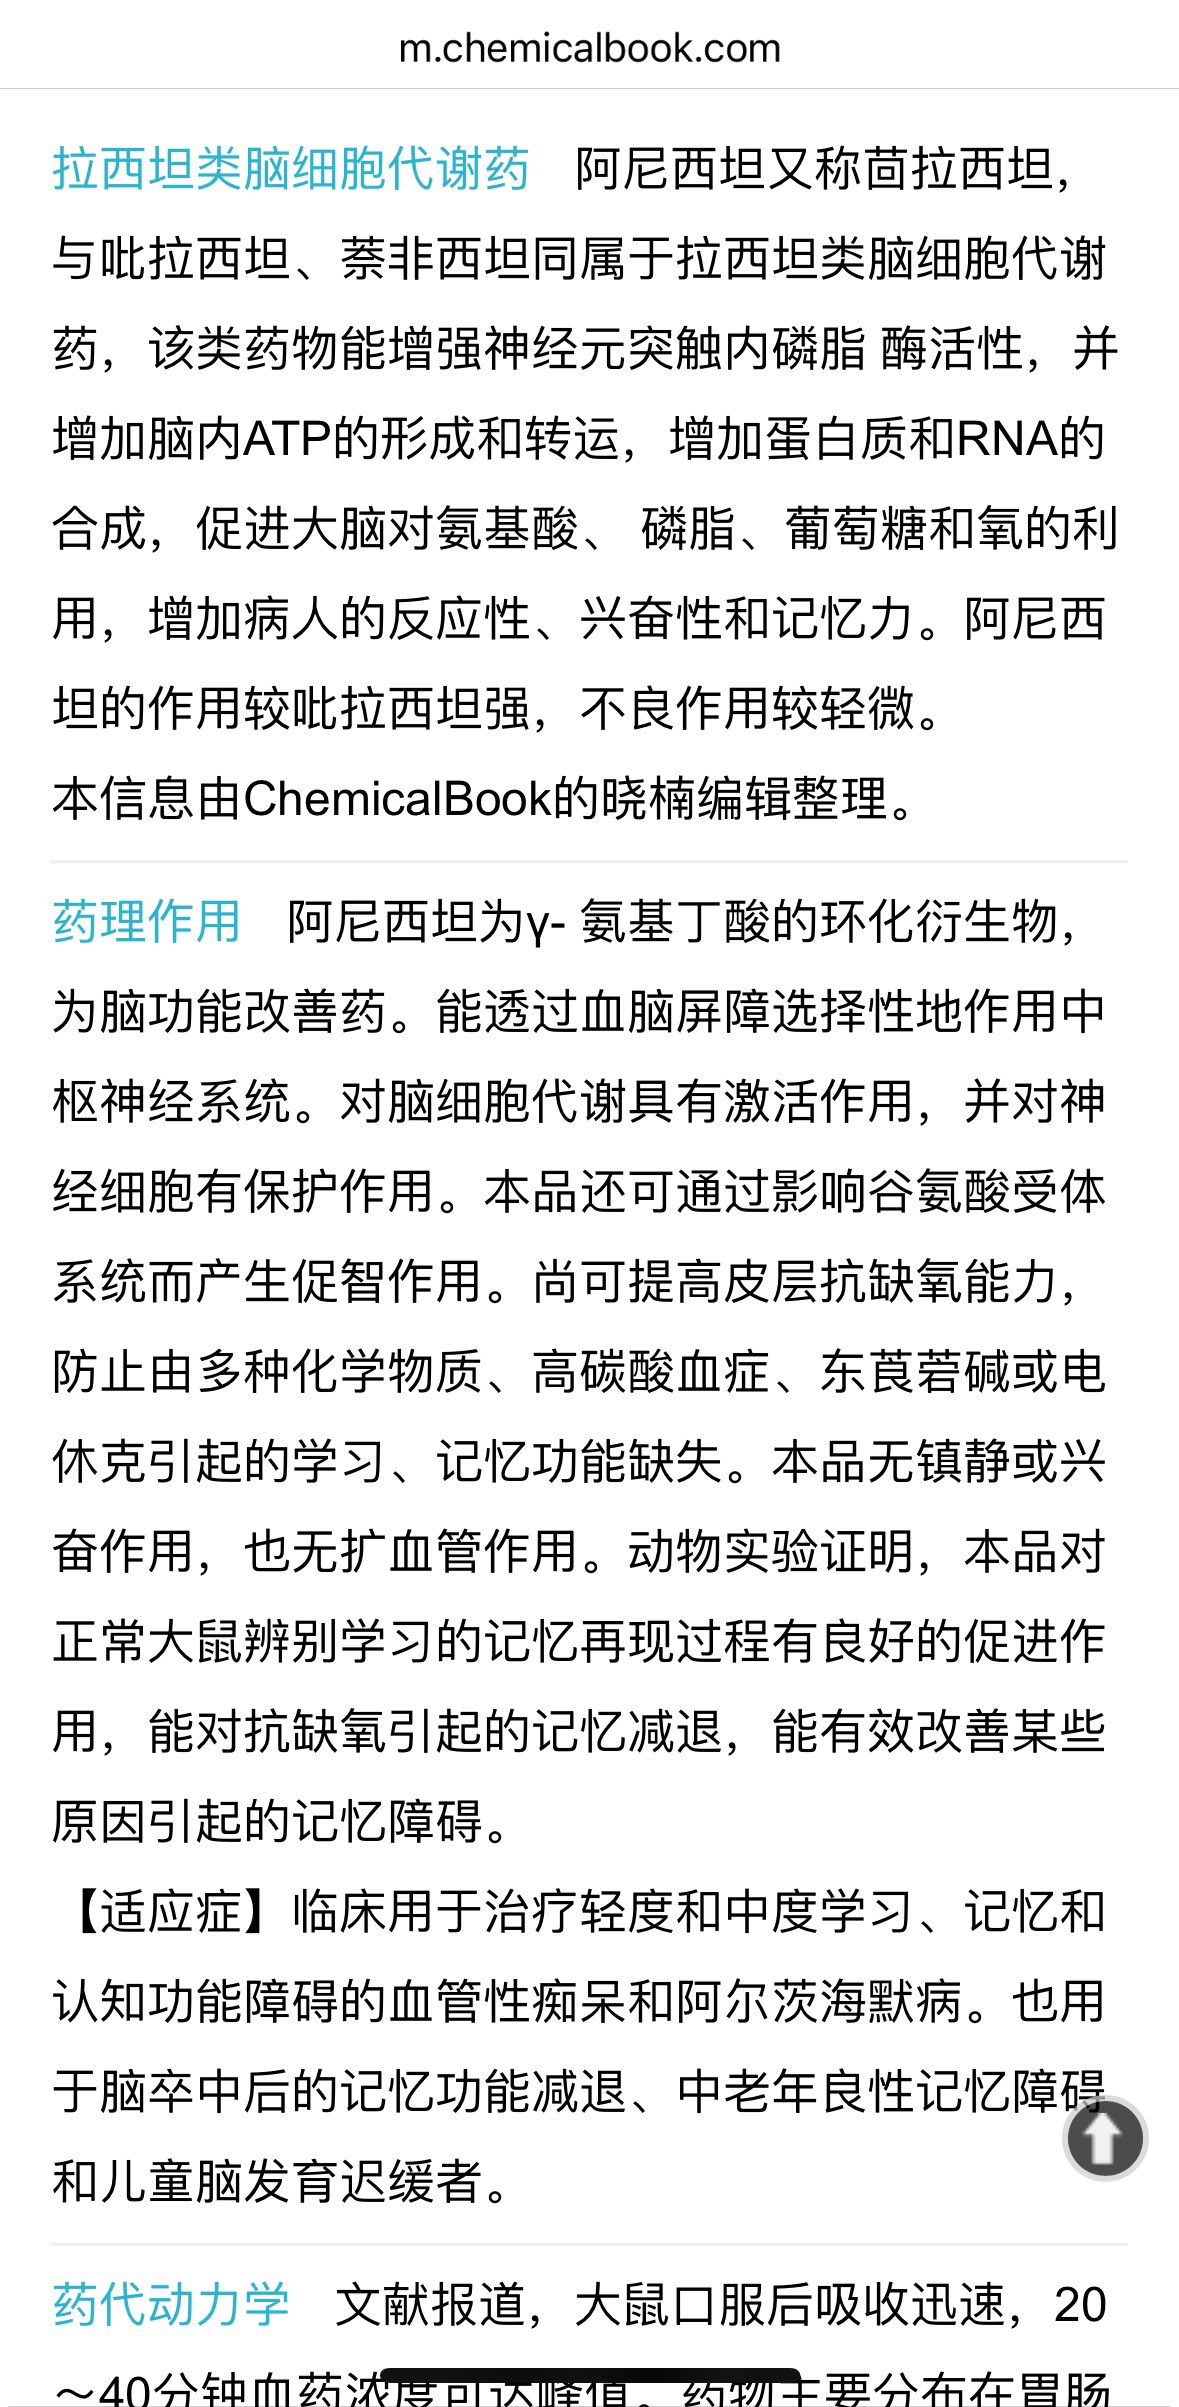

首先,从定义上讲,“反解离(anti-dissociative)”并不是一个标准的医学术语或者广泛认同的药理学分类。在正规资料,比如医学文献、维基百科、精神药理学教科书中,目前并没有“反解离药物”这个正式概念。

看上去像是为了描述某类特定效应而创造的术语(可能是nmda受体活性增强),用来对抗因NMDA受体拮抗剂(比如氯胺酮、DXM、PCP等)引发的解离体验(dissociation)。

那么更常见的是将其归入认知增强剂(cognitive enhancers),特别是改善认知连接性(connectivity)和现实感知(reality testing)的类型。

但其实在药理学上,单纯用“受体激动剂”来逆转“受体拮抗剂”的效应,有时会导致过度激活。

对于NMDA受体而言,过强的NMDA活化本身就与兴奋性毒性(excitotoxicity)和精神病样症状(psychotomimetic effects)有关,比如谷氨酸风暴可以引发严重的焦虑、妄想、乃至癫痫。

也就是说,简单地“激动-解除拮抗”在中枢神经系统是很危险的做法,尤其是对于易感个体(如有精神分裂素质的人)。

科学的处理方式一般是通过更细致的调节,比如微调NMDA/AMPA平衡、调节其他辅助途径(如GABA、5-HT、mGluR受体),而不是简单粗暴地用“NMDA增强剂”去顶回去。

而临床处理药物中毒中,其实医生更常用的做法是保守、支持性的治疗,比如补液,促进代谢,必要时镇静,以及监测生命体征防治并发症。

药物拮抗与受体激动之间,往往牵扯到的是复杂的适应性变化(receptor upregulation/downregulation),

不是简单的“给多一点刺激就能抵消”的关系